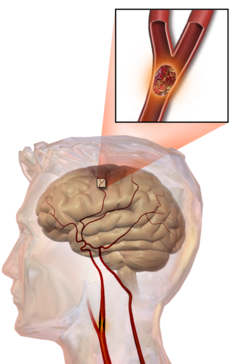

Illustration of an embolic stroke, showing a blockage lodged in a blood vessel

In thrombotic stroke, a thrombus[41] (blood clot) usually forms around atherosclerotic plaques. Since blockage of the artery is gradual, onset of symptomatic thrombotic stroke is slower than that of hemorrhagic stroke. A thrombus itself (even if it does not completely block the blood vessel) can lead to an embolic stroke (see below) if the thrombus breaks off and travels in the bloodstream, at which point it is called an embolus. Two types of thrombosis can cause stroke:

Embolic stroke

An embolic stroke refers to an arterial embolism (a blockage of an artery) by an embolus, a traveling particle or debris in the arterial bloodstream originating from elsewhere. An embolus is most frequently a thrombus, but it can also be a number of other substances including fat (e.g., from bone marrow in a broken bone), air, cancer cells or clumps of bacteria (usually from infectious endocarditis).[49]

Because an embolus arises from elsewhere, local therapy solves the problem only temporarily. Thus, the source of the embolus must be identified. Because the embolic blockage is sudden in onset, symptoms are usually maximal at the start. Also, symptoms may be transient as the embolus is partially resorbed and moves to a different location or dissipates altogether.